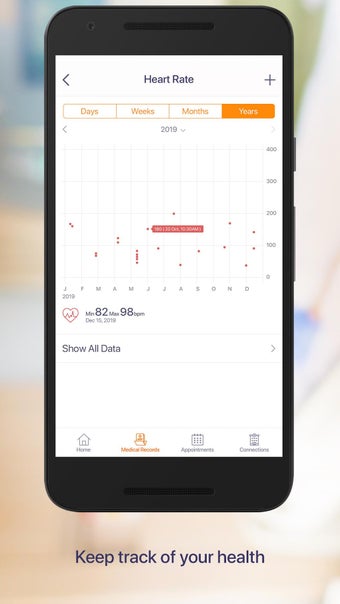

Carepassport là một ứng dụng Android cung cấp cho bệnh nhân một giải pháp toàn diện để quản lý dữ liệu y tế của họ. Ứng dụng cho phép bệnh nhân truy cập và lưu trữ an toàn dữ liệu y tế của mình, lên lịch hẹn, xem hình ảnh y tế, báo cáo xét nghiệm và lâm sàng từ các nhà cung cấp khác nhau, và chia sẻ chúng bằng công nghệ tính toán di động tiên tiến. Với Carepassport, bệnh nhân có thể dễ dàng quản lý nhu cầu chăm sóc sức khỏe của mình chỉ với vài lần chạm trên thiết bị di động của họ.

Một trong những tính năng quan trọng nhất của ứng dụng là việc truy cập dữ liệu y tế một chạm dễ dàng. Bệnh nhân có thể truy cập dữ liệu y tế của mình hoặc dữ liệu đại diện gia đình một cách an toàn và nhanh chóng, làm cho nó trở thành một công cụ tuyệt vời để quản lý lịch sử bệnh án của họ. Ứng dụng cũng cho phép người dùng tìm kiếm các phòng khám và bệnh viện gần đó, lên lịch hẹn, và thậm chí nhận chỉ đường đến cuộc hẹn của họ qua Uber. Ngoài ra, bệnh nhân có thể giao tiếp với nhà cung cấp chăm sóc của họ qua tin nhắn an toàn, chia sẻ hình ảnh y tế và cho phép thành viên gia đình truy cập dữ liệu y tế của họ thông qua cài đặt proxy an toàn. Cuối cùng, ứng dụng cung cấp tài liệu giáo dục liên quan đến chăm sóc sức khỏe và có thể kết nối với các thiết bị đeo được hoặc nhập dữ liệu y tế thủ công.